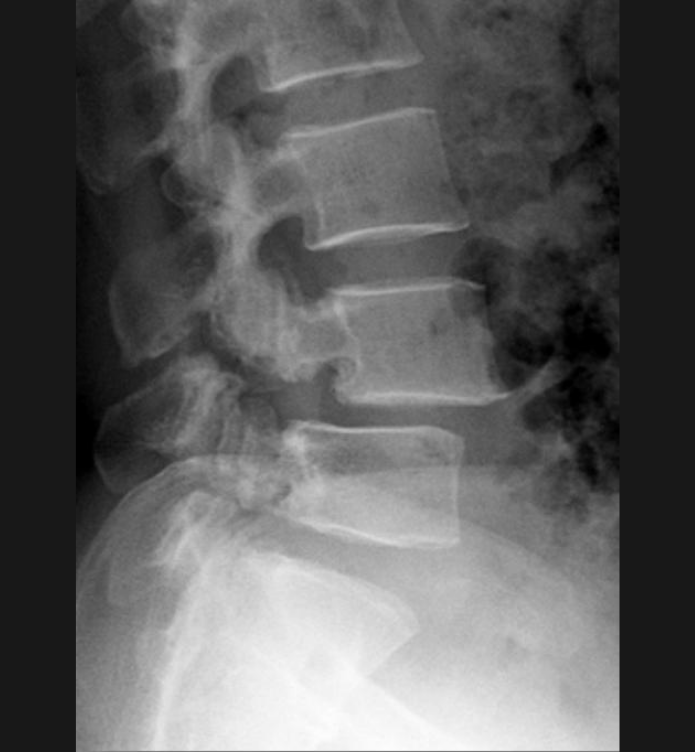

Basit Omurga ve Omurilik Anatomisi Omurga, 33 adet omur kemiğinden oluşur. Bu kemiklerin 7 tanesi boyun omuru, 12 tanesi sırt omuru, 5 tanesi bel omurudur. Beş tanesi birleşmiş olarak sakrum denilen kemiği ve 4 tanesi yine birleşmiş olarak koksiks denilen kuyruk sokumu kemiğini oluşturur. Omurganın görevi omuriliği korumak ve gövdeyi dik pozisyonda tutmak için destek […]